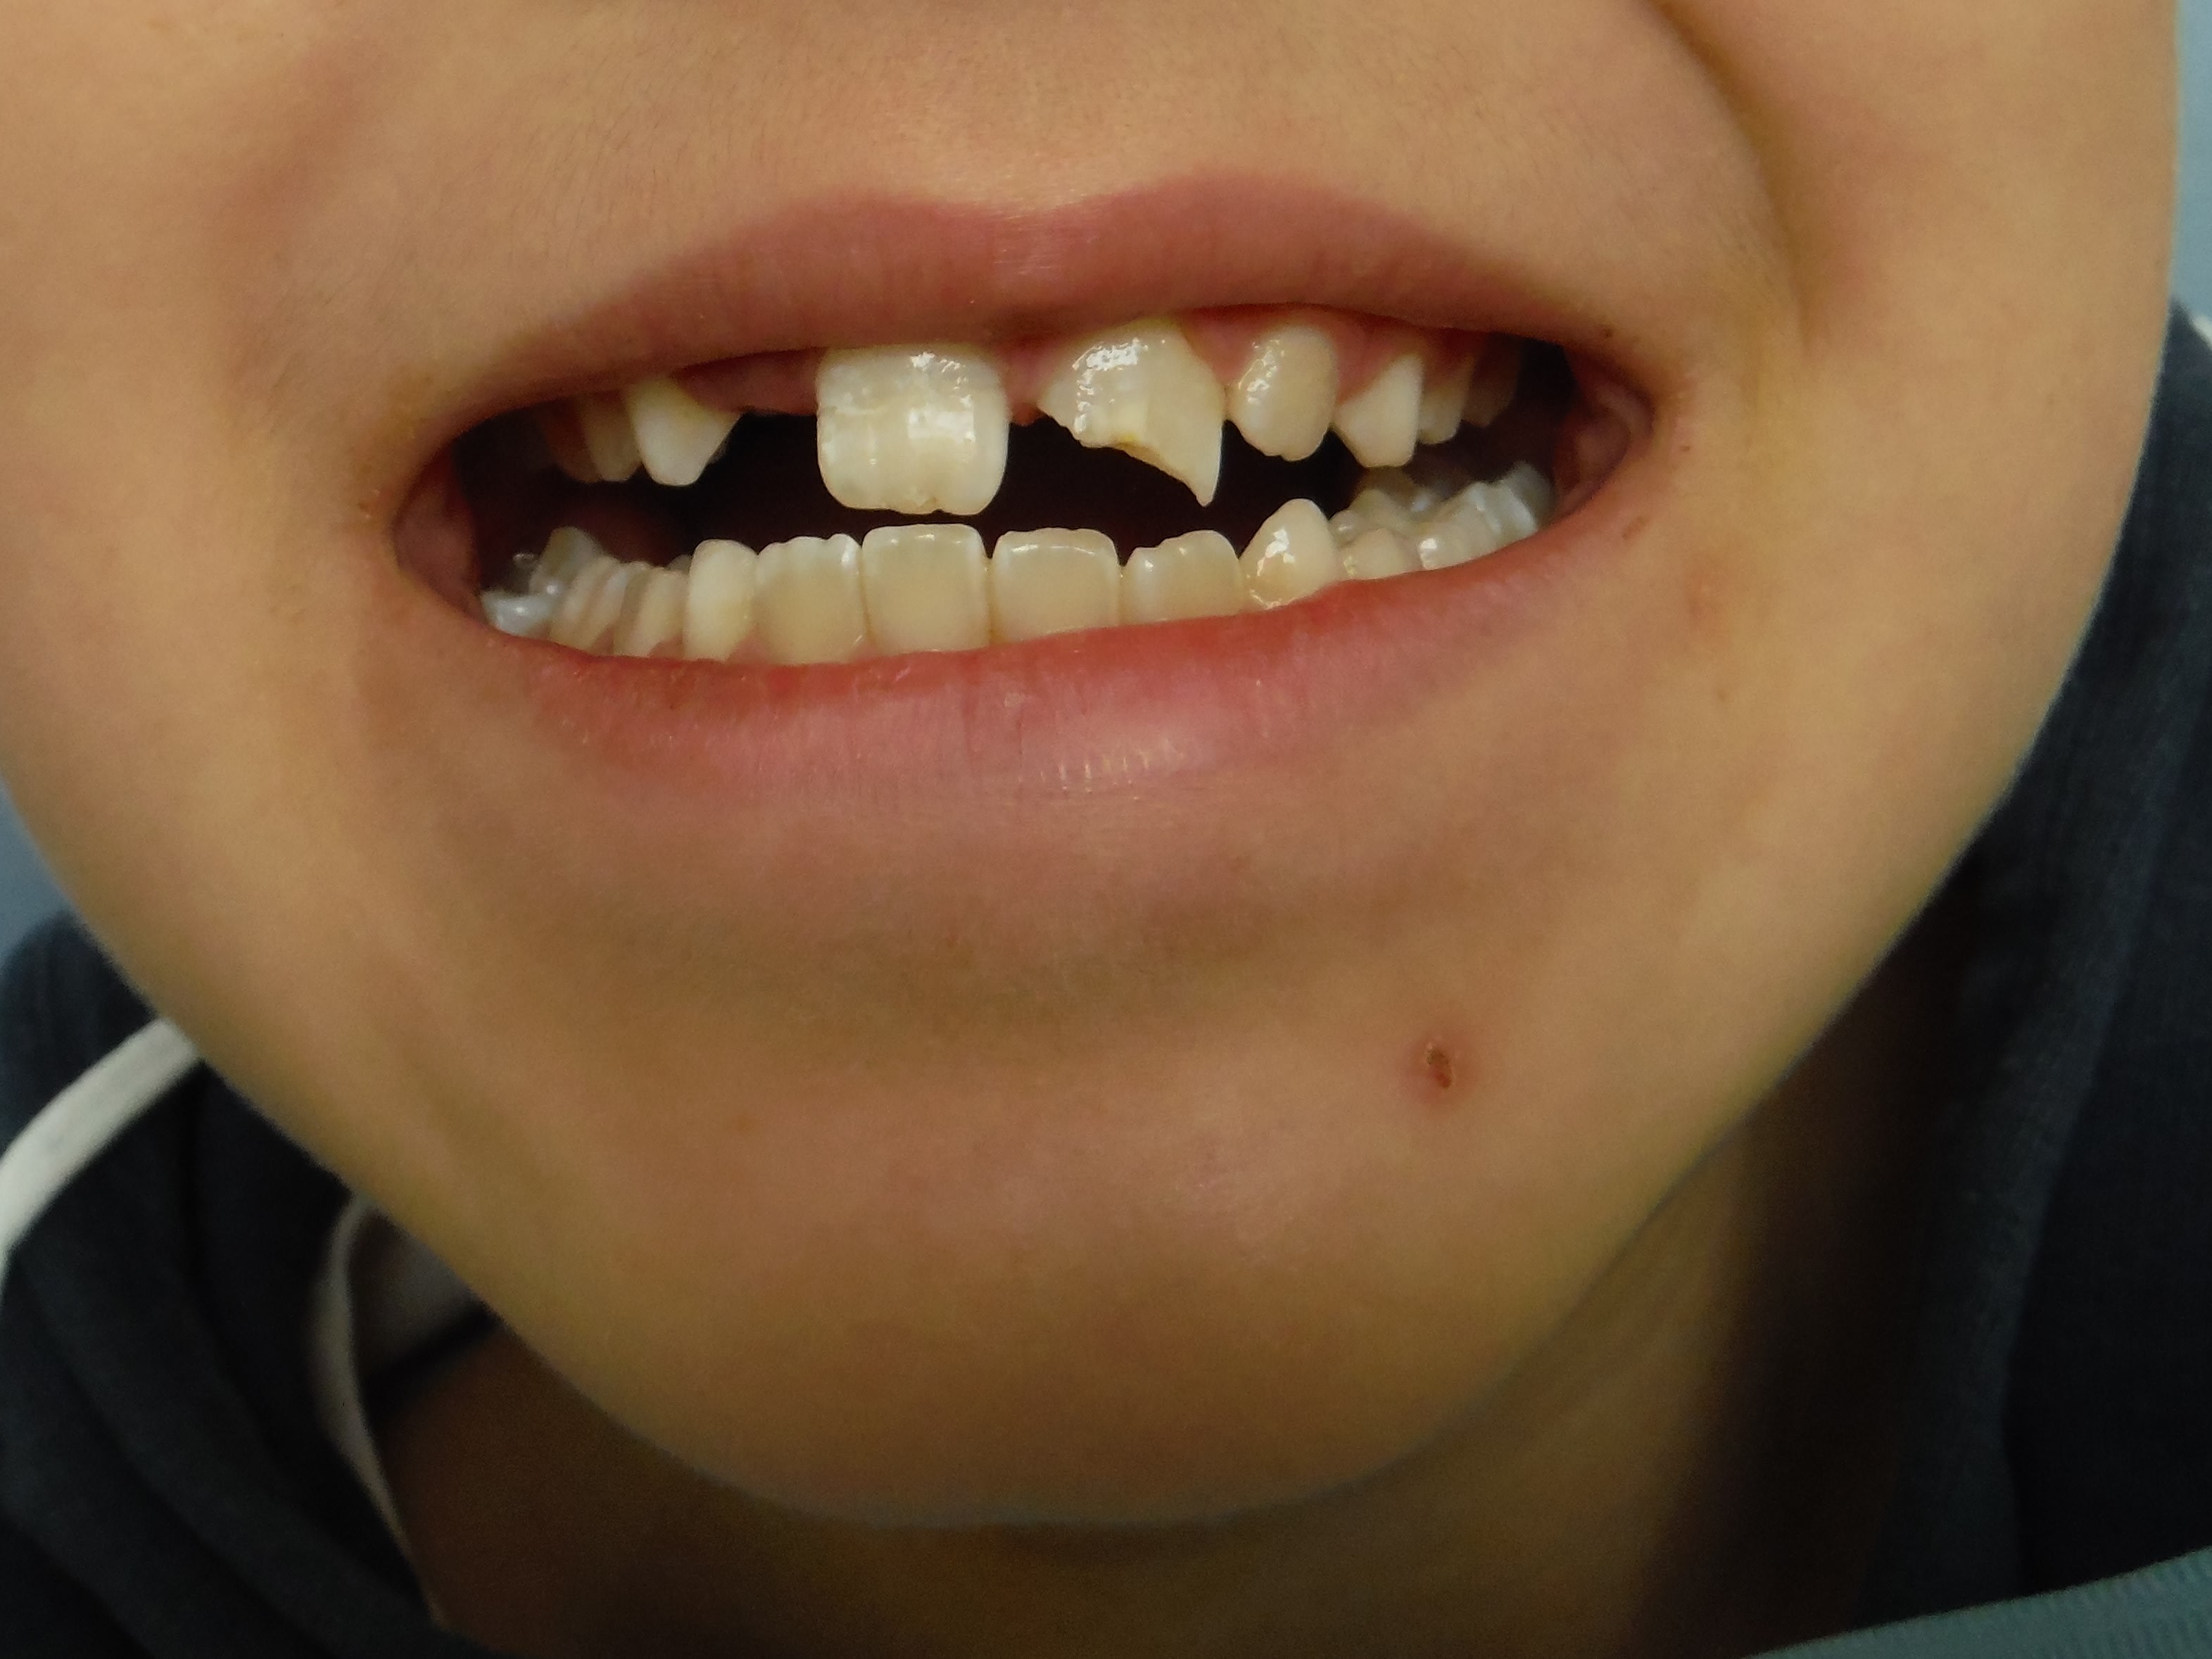

Le truc qui te met bien à l'heure. Et encore! j'ai pensé à faire la photo après avoir recollé le fragment de la 11. Pour la 21, fragment perdu, compo à main levée. Récréation... 8 ans, des apex ouverts et des cornes pulpaires pas loin des fractures... à suivre.

5 ans, première rencontre avec un dentiste....